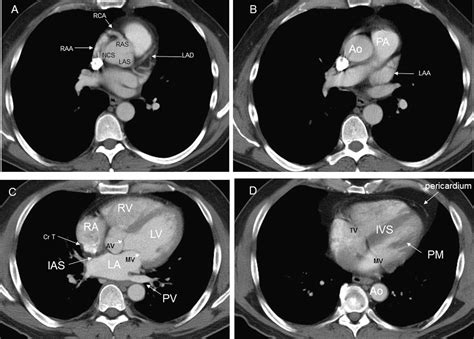

Cardiovascular health remains a top priority for medical professionals and patients alike, especially as diagnostic technology continues to evolve. When doctors need to get a clear, detailed look at the coronary arteries to assess the risk of heart disease, they often turn to advanced imaging techniques. A Ct Scan For Heart, clinically known as a Coronary Computed Tomography Angiography (CCTA) or a Coronary Artery Calcium (CAC) scan, has become a cornerstone in modern preventative cardiology. By providing high-resolution images of the heart's structure and its surrounding blood vessels, this non-invasive procedure allows physicians to identify potential blockages or calcification long before a patient experiences a major cardiac event.

The primary purpose of a Ct Scan For Heart is to evaluate the health of the coronary arteries. These vessels are responsible for supplying oxygen-rich blood to the heart muscle. Over time, these arteries can accumulate plaque—a buildup of fat, cholesterol, calcium, and other substances. If left unchecked, this plaque can harden or rupture, leading to restricted blood flow and an increased risk of heart attacks. Unlike traditional stress tests, which measure how the heart functions under pressure, a CT scan provides a direct visualization of the anatomy, allowing for a precise "map" of the arterial state.

• Coronary Artery Calcium (CAC) Scan: This non-contrast scan measures the amount of calcified plaque in the arteries. It provides a "Calcium Score," which helps doctors estimate the overall risk of heart disease.

• Coronary CT Angiography (CCTA): This scan utilizes an iodine-based contrast dye to highlight the interior of the arteries, allowing radiologists to see not only calcified plaque but also "soft" plaque that could potentially block blood flow.

Once the scan is complete, a specialized radiologist or cardiologist will analyze the hundreds of images produced to identify any narrowing of the arteries or presence of plaque. The results are typically compiled into a report that quantifies the extent of atherosclerosis. If your calcium score is high or significant blockages are found, your doctor will move from a preventative approach to an active management plan. This might include aggressive lipid-lowering therapies (such as statins), lifestyle interventions like specific exercise programs, or further invasive procedures if the blockage is deemed critical.